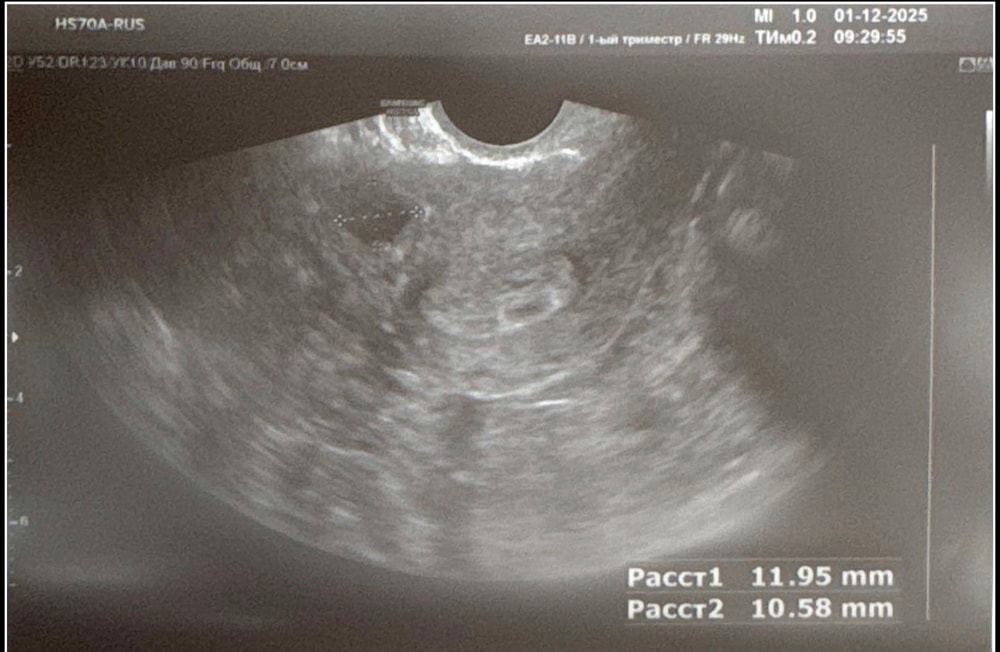

ЭКО 40+. Второй протокол. 18ДПП первое узи.

Моя ЭКО-история (от начала пути до родов)Вот мы и докатились до первого узи. Перенос был 13.11, две четырехдневки (с дс). Акушерский срок сегодня 5 нед. 1 д.

Сдавала ХГЧ три раза на 9, 11 и 13 дпп (62,168,514 ед.). На сегодня узи назначила моя репродуктолог. Но смотрела не она, а поликлиника, в которой я обслуживаюсь.

Итого, что имеем:

Первый вопрос, который у меня возник: возможно ли появление второго плодного яйца позже? У кого был опыт, откликнетесь пжста 🙏🏻

Второй конечно шо это за кистозные дела и откуда они взялись? Но буду спрашивать своего дока коррелирует ли это с двумя стимуляциями, которые я с горем пополам прожила с середины июля. Потом решим что с этим делать.

В остальном понимаю что ещё очень рано делать какие бы то ни было выводы, но вроде как пока все укладывается в норму.

Напоследок пару свежих фоточек😎